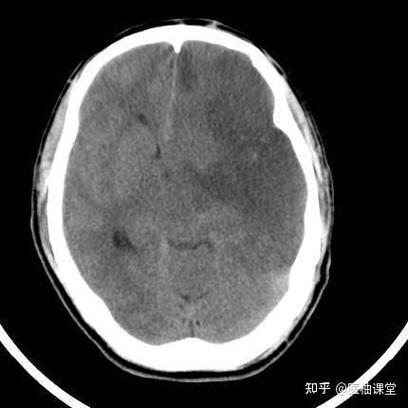

(图片来源网络,侵删)

- 这次检查的“新发现”:这次您去做脑CT,可能是因为头晕、头痛、肢体麻木、无力或其他神经系统症状,医生在做这次检查时,意外地发现了您大脑里有一些陈旧性的病灶,这些病灶是之前发生过脑梗死的痕迹,就像皮肤上留下的旧疤痕一样。

- “陈旧性”是关键:这个词非常重要,说明这次的梗塞是过去发生的,而不是正在进行的急性期,如果您是刚刚发生脑梗,CT上可能不会立刻显示出典型的梗塞灶(通常需要24小时后才能清晰看到),而且您当时肯定会有非常典型的急性症状,如口角歪斜、肢体瘫痪、失语等,需要立即急诊。

- 您可能没有察觉:很多“陈旧性脑梗塞”是在发生时症状非常轻微,甚至完全没有症状(医学上称为“无症状性脑梗塞”或“静息性脑梗塞”),所以您自己可能都不知道曾经发生过,这种情况在老年人中尤其常见。